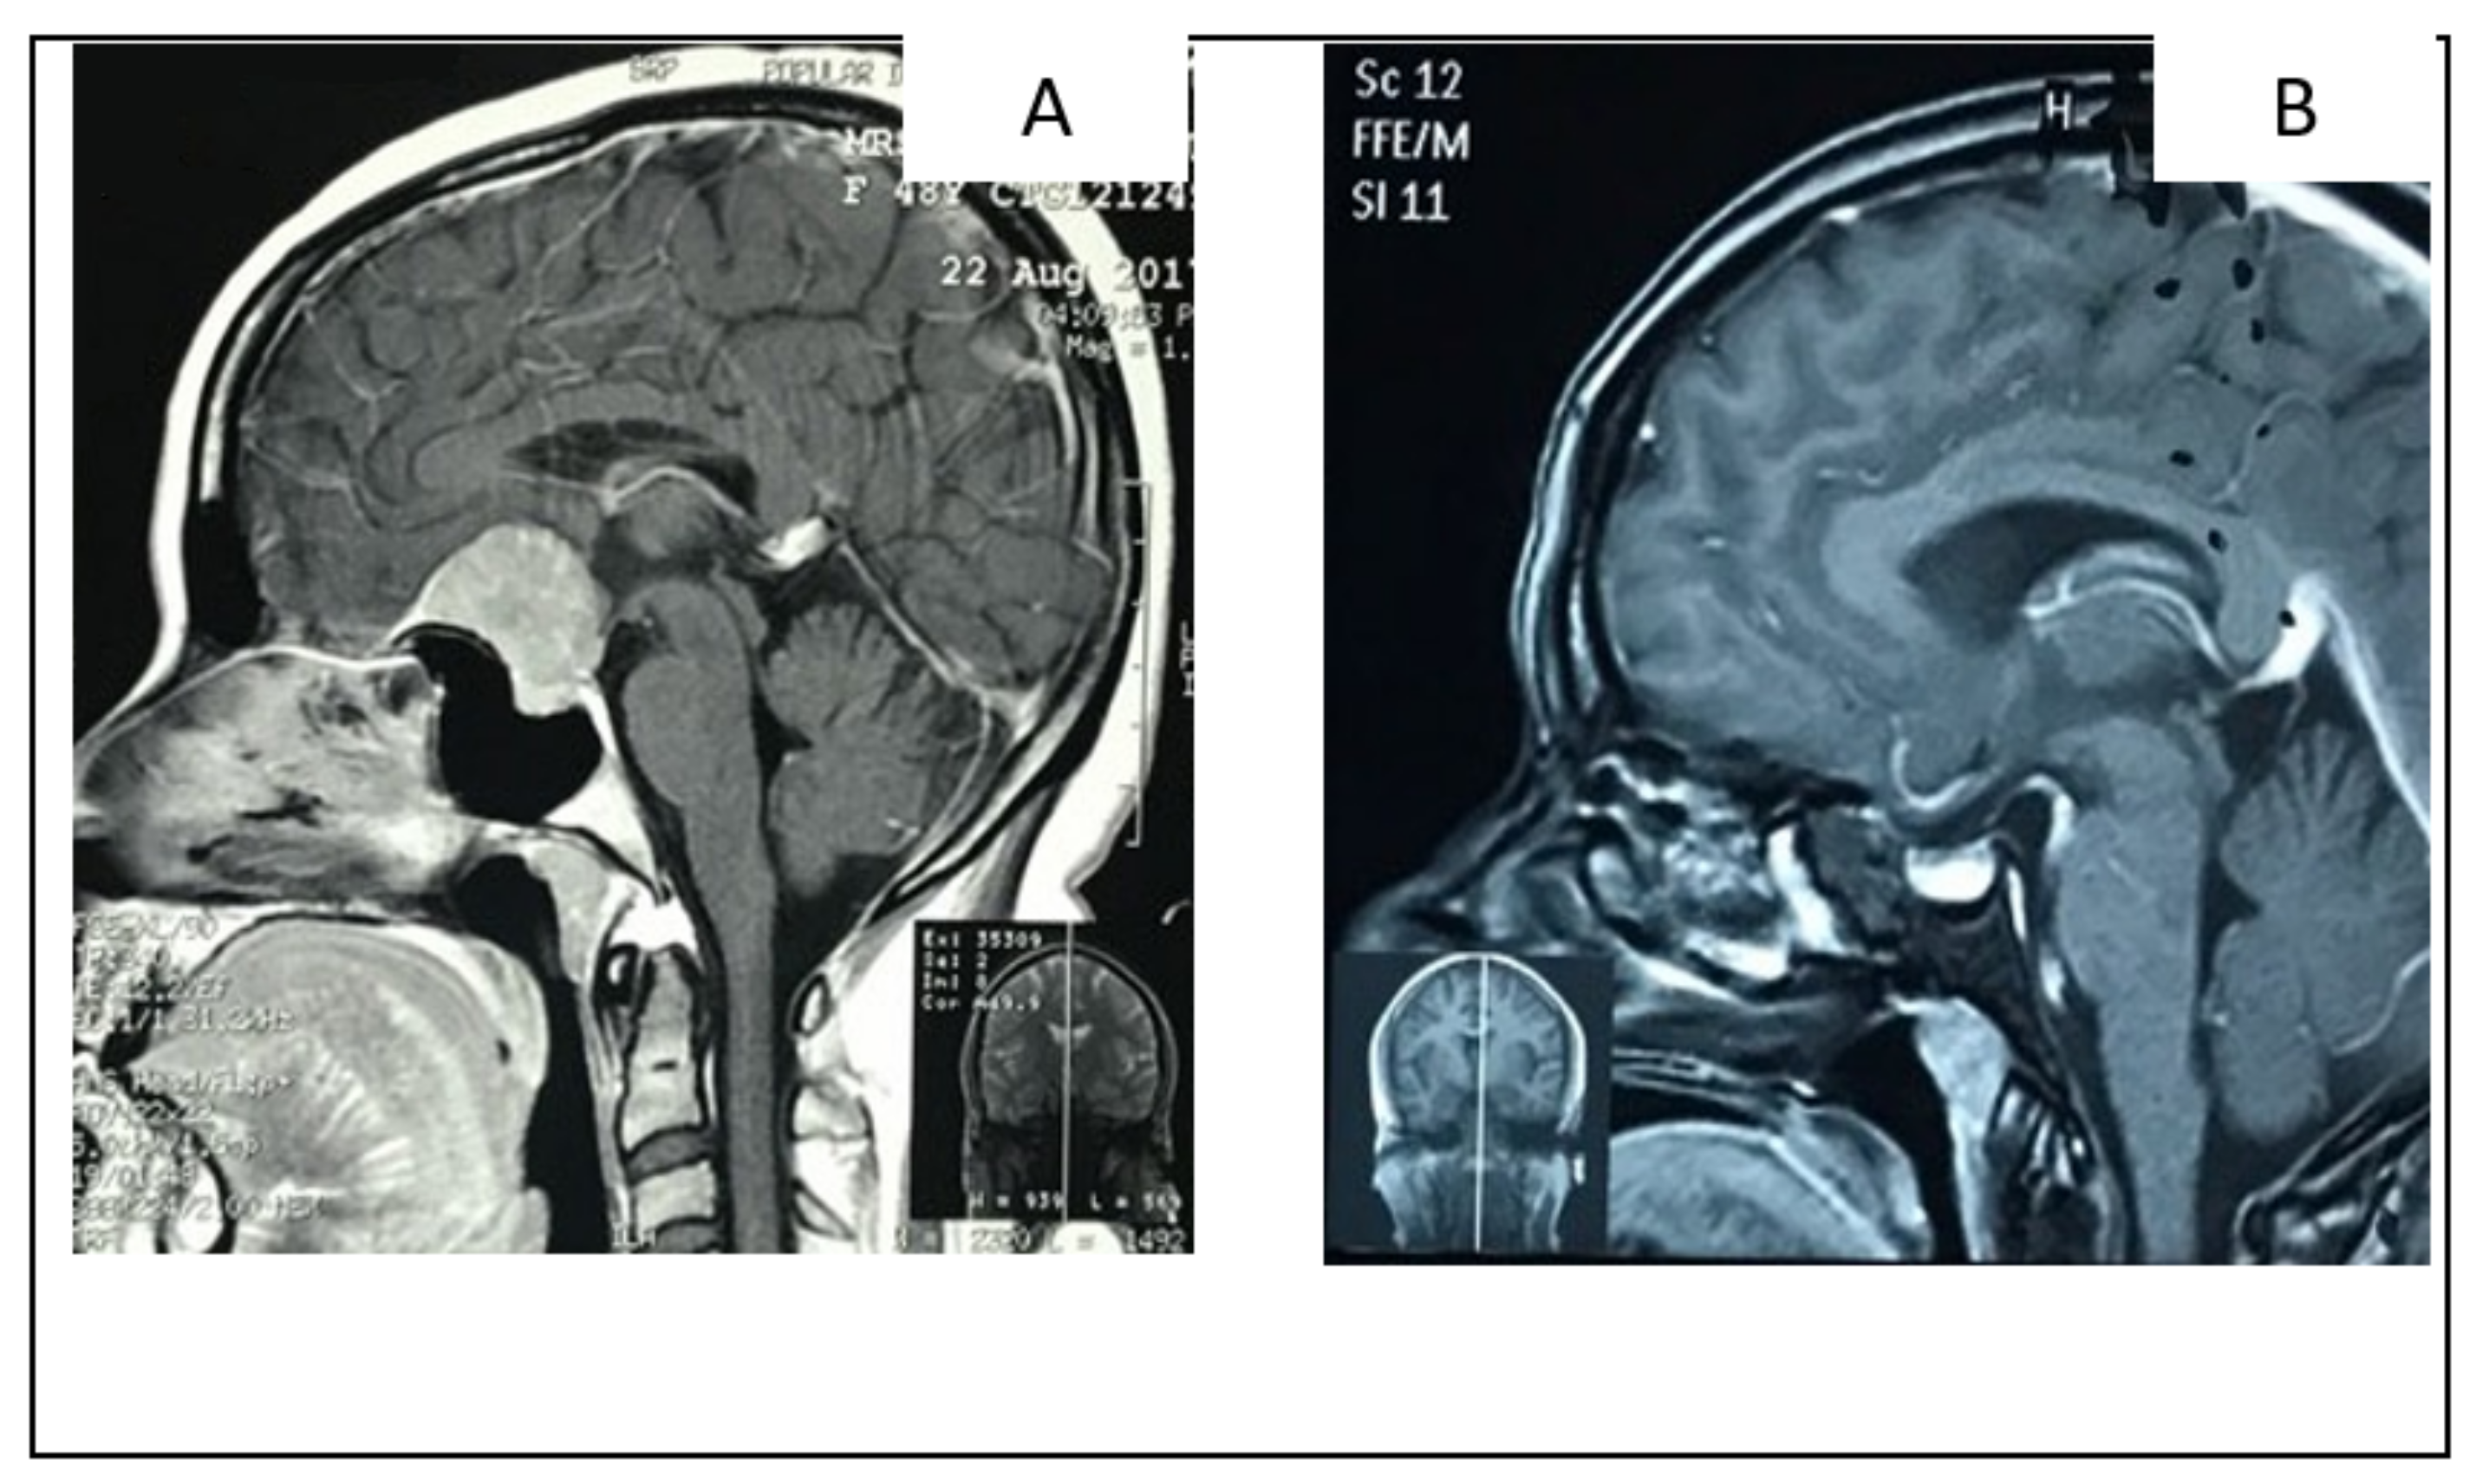

2.5.2. Illustrative Case 5